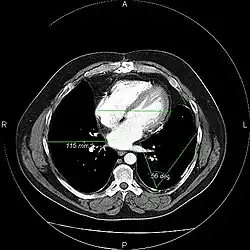

An image as stored on a picture archiving and communication system (PACS)

The same image following contrast adjustment, sharpening and measurement tags added by the system